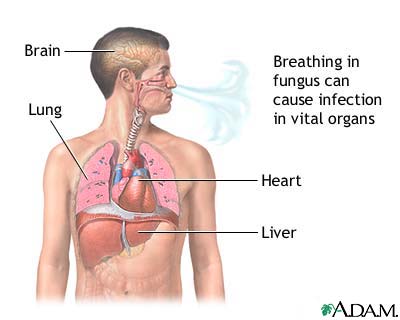

Valley fever is an infection that occurs when the spores of the fungus Coccidioides immitis or Coccidioides posadasii enter your body through the lungs.

Valley fever is due to a fungal infection most commonly seen in the desert regions of the southwestern United States, and in Central and South America. You get it by breathing in the fungus from soil. The infection starts in the lungs. It commonly affects people over 60 years of age.

Rarely, the infection spreads from the lungs through the bloodstream to involve the skin, bones, joints, lymph nodes, and central nervous system or other organs. This spread is called disseminated coccidioidomycosis.